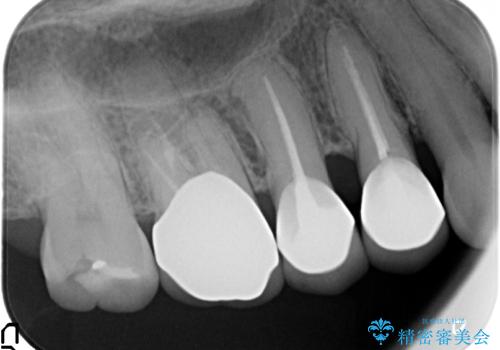

古くなったセラミッククラウンのやりかえ

- 老朽化し黒ずんできたクラウンのやりかえを希望され来院されました。

将来的に歯ぐきの位置が変化しても審美障害となりづらいオールセラミックジルコニアクラウンによるやり替えを計画します。